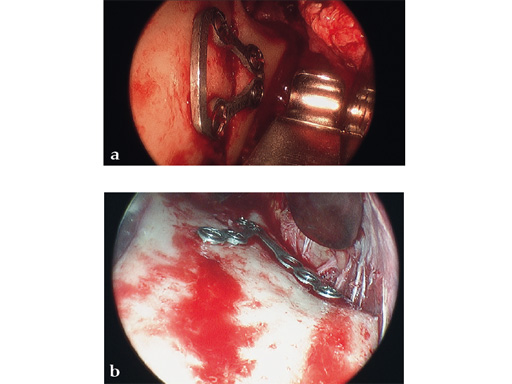

Lambda Plate

The lambda plate comes in a left and right version. It emulates a two-plate technique as its specific shape and 7-hole design with the width of a single plate at the top segment allows the surgeon to advance the lambda plate high up into the very narrow zone of the condylar neck just below the head. The fixation arms straddle the mandibular canal to avoid injury risk of the inferior alveolar nerve.

The lambda plate can be placed using retromandibular or submandibular surgical approaches. For positioning, the straight 5-hole segment is placed parallel to the posterior ramus border aligned with the condylar head. If required the anterior arm may be bent to fit the bony surface below the sigmoid notch.